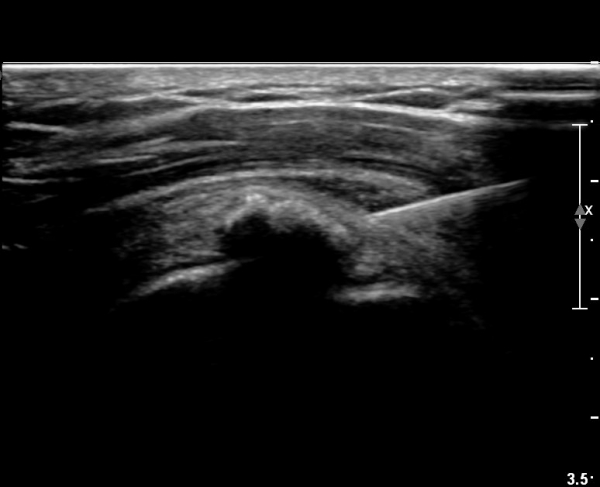

ÃÊÀ½ÆÄ ¼Ò°ß :  ±Ø»ó°Ç Á¾´Ü¸é°Ë»ç¿¡¼­ ÈĹæÀ½¿µÀ» º¸ÀÌ´Â °í¿¡ÄÚ ¼®È¸È­ µ¢¾î¸®°¡ °üÂûµÈ´Ù(»çÁø 1).

±Ø»ó°Ç Ⱦ´Ü¸é°Ë»ç¿¡¼­µµ ±Ø»ê°Ç³» ¼®È¸È­ µ¢¾î¸®°¡ °üÂûµÈ´Ù(»çÁø 2).